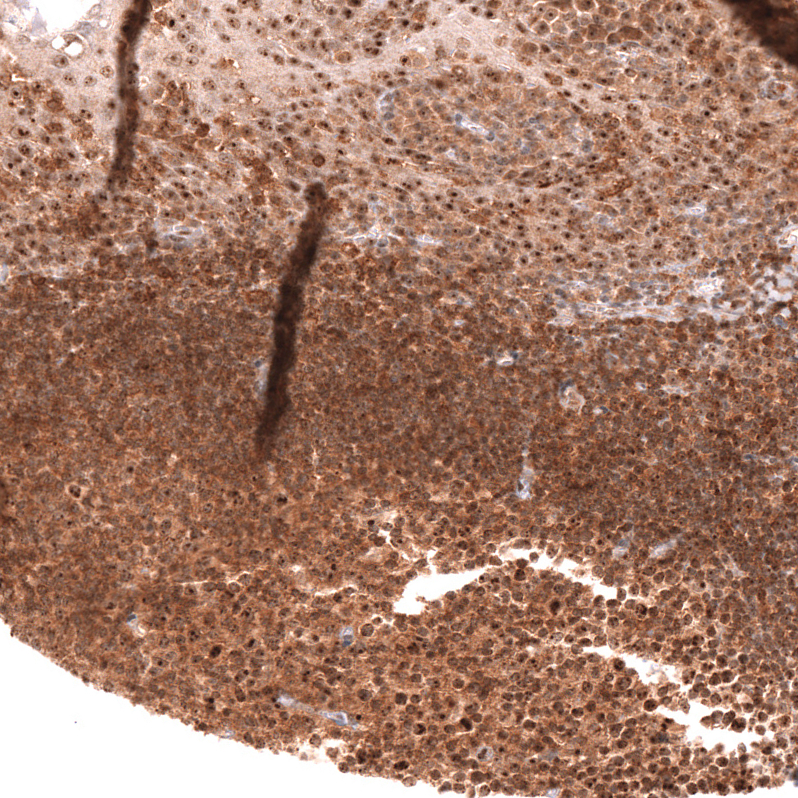

Immunohistochemistry analysis in human tonsil and liver tissues using AMAb91946 antibody. Corresponding TFEB RNA-seq data are presented for the same tissues.